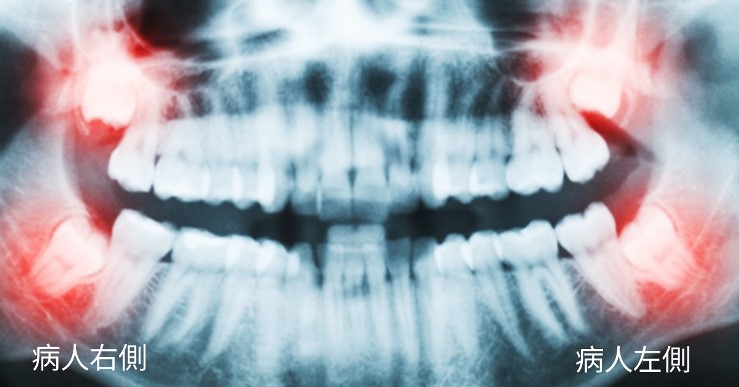

智齒是我們的第三大臼齒(見下圖),一般來說,智齒大約是在 9 ~ 10歲的時候可以在 X光片中看到牙胚,智齒冒出頭可在口腔內見到的大約時間是從 17 ~ 18歲,一直到 25歲都有可能生長完成。

請見下圖 X光影像,可以發現 4顆智齒,牙根發育接近完成。